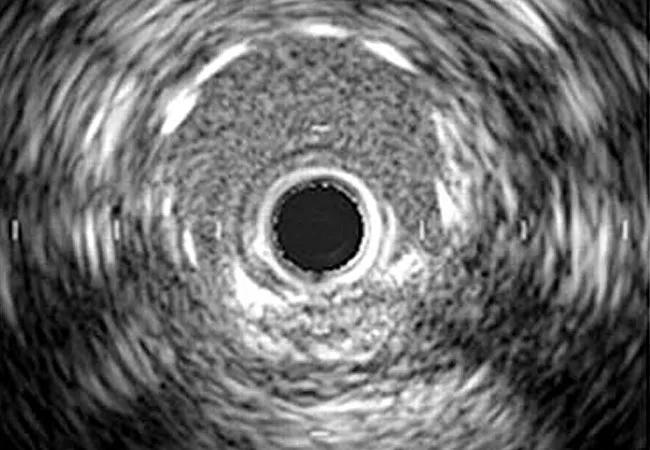

Does the superiority of intravascular ultrasound (IVUS) over angiography for guiding percutaneous coronary intervention (PCI) apply in the era of drug-eluting stents?

Dr. Ellis: Angiography is the traditional modality for visualizing the severity of coronary lesions before, during and after PCI. Yet operators are aware that angiography doesn’t allow for sufficient visual assessment of a coronary lesion. IVUS is a more sensitive tool that allows for optimization of stent implantation by ensuring good stent expansion and apposition.

Dr. Ellis: It does. You can see how well the stent is expanded, and the minimum lumen area in the stented segment is strongly correlated with the need for revascularization. You may think you have a good result, but you may need to go back in.